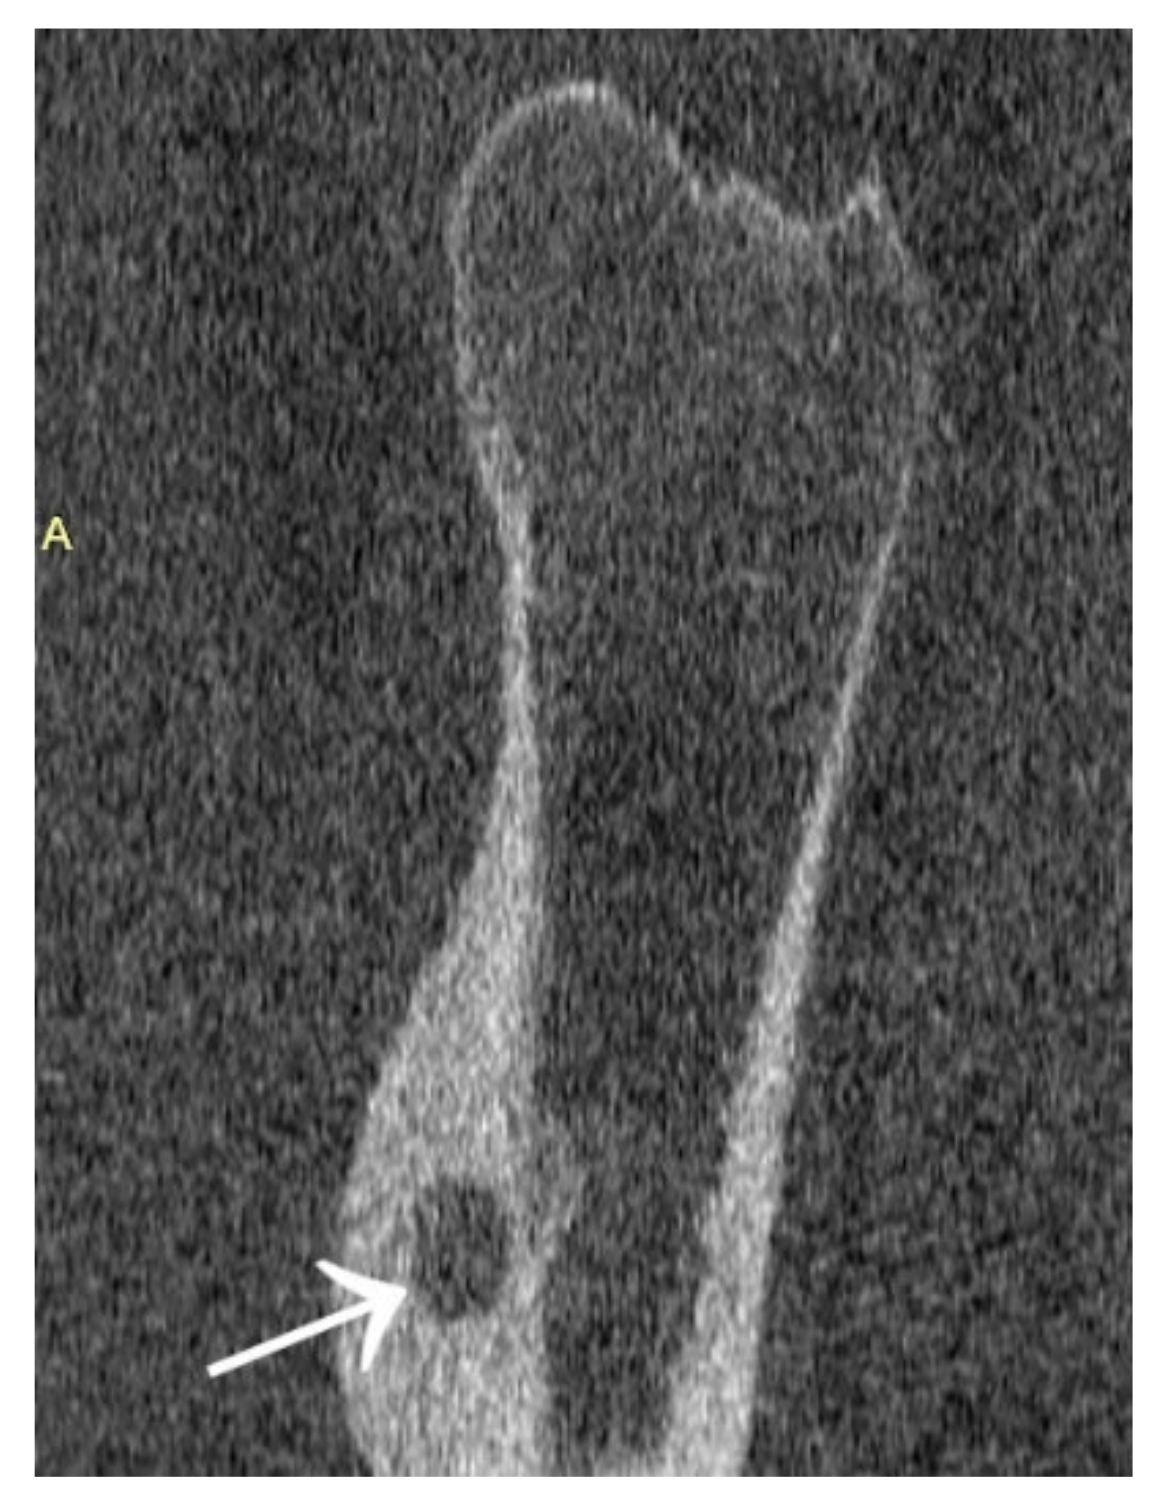

3.4. Case 4: OO Masking as a Fatigue Fracture